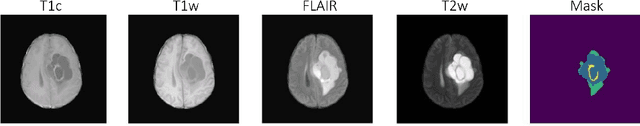

Abstract:Gliomas are the most prevalent type of primary brain tumors, and their accurate segmentation from MRI is critical for diagnosis, treatment planning, and longitudinal monitoring. However, the scarcity of high-quality annotated imaging data in Sub-Saharan Africa (SSA) poses a significant challenge for deploying advanced segmentation models in clinical workflows. This study introduces a robust and computationally efficient deep learning framework tailored for resource-constrained settings. We leveraged a 3D Attention UNet architecture augmented with residual blocks and enhanced through transfer learning from pre-trained weights on the BraTS 2021 dataset. Our model was evaluated on 95 MRI cases from the BraTS-Africa dataset, a benchmark for glioma segmentation in SSA MRI data. Despite the limited data quality and quantity, our approach achieved Dice scores of 0.76 for the Enhancing Tumor (ET), 0.80 for Necrotic and Non-Enhancing Tumor Core (NETC), and 0.85 for Surrounding Non-Functional Hemisphere (SNFH). These results demonstrate the generalizability of the proposed model and its potential to support clinical decision making in low-resource settings. The compact architecture, approximately 90 MB, and sub-minute per-volume inference time on consumer-grade hardware further underscore its practicality for deployment in SSA health systems. This work contributes toward closing the gap in equitable AI for global health by empowering underserved regions with high-performing and accessible medical imaging solutions.

Abstract:Automating brain tumor segmentation using deep learning methods is an ongoing challenge in medical imaging. Multiple lingering issues exist including domain-shift and applications in low-resource settings which brings a unique set of challenges including scarcity of data. As a step towards solving these specific problems, we propose Convolutional adapter-inspired Parameter-efficient Fine-tuning (PEFT) of MedNeXt architecture. To validate our idea, we show our method performs comparable to full fine-tuning with the added benefit of reduced training compute using BraTS-2021 as pre-training dataset and BraTS-Africa as the fine-tuning dataset. BraTS-Africa consists of a small dataset (60 train / 35 validation) from the Sub-Saharan African population with marked shift in the MRI quality compared to BraTS-2021 (1251 train samples). We first show that models trained on BraTS-2021 dataset do not generalize well to BraTS-Africa as shown by 20% reduction in mean dice on BraTS-Africa validation samples. Then, we show that PEFT can leverage both the BraTS-2021 and BraTS-Africa dataset to obtain mean dice of 0.8 compared to 0.72 when trained only on BraTS-Africa. Finally, We show that PEFT (0.80 mean dice) results in comparable performance to full fine-tuning (0.77 mean dice) which may show PEFT to be better on average but the boxplots show that full finetuning results is much lesser variance in performance. Nevertheless, on disaggregation of the dice metrics, we find that the model has tendency to oversegment as shown by high specificity (0.99) compared to relatively low sensitivity(0.75). The source code is available at https://github.com/CAMERA-MRI/SPARK2024/tree/main/PEFT_MedNeXt